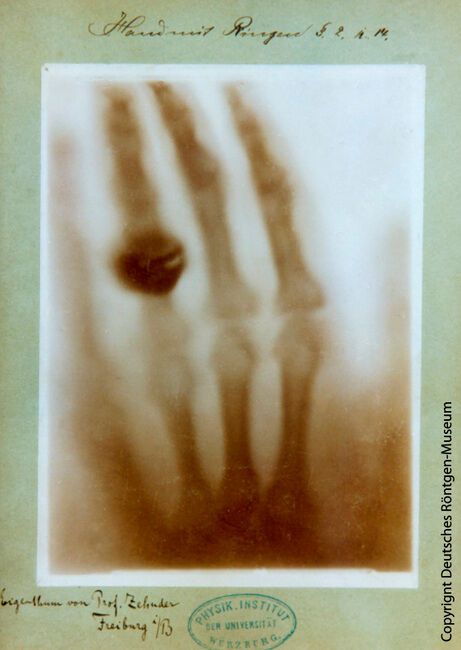

Die erste veröffentlichte und zeitlich genau dokumentierte Röntgenaufnahme war die Hand von Wilhelm Conrad Röntgens Frau Bertha. Die Aufnahme stammt vom 22. Dezember 1895.(Bild:  Deutsches Röntgen-Museum)

Die erste veröffentlichte und zeitlich genau dokumentierte Röntgenaufnahme war die Hand von Wilhelm Conrad Röntgens Frau Bertha. Die Aufnahme stammt vom 22. Dezember 1895.

In Würzburg machte Wilhelm Conrad Röntgen am 8. November 1895 seine berühmte Entdeckung der „X-Strahlen“ im Zuge seiner Forschung über Kathodenstrahlung. Mit seinen Strahlen ermöglichte Röntgen es, das bis dahin verborgene Innere eines Organismus sichtbar zu machen und zu betrachten. Die erste veröffentlichte und zeitlich genau dokumentierte Röntgenaufnahme war eine, die die Hand seiner Frau Bertha zeigte. Sie stammt vom 22. Dezember 1895. Die Nachricht von Röntgens revolutionärer Entdeckung verbreitete sich in Fachwelt und Öffentlichkeit sehr schnell. Röntgen wurde für seine Entdeckung am 10. Dezember 1901 bei der ersten Verleihung der Nobelpreise mit dem Nobelpreis für Physik geehrt. Den in den Statuten geforderten Vortrag bei der Verleihung hat er aufgrund seines „Lampenfiebers“, wie er schrieb, nie gehalten. Überhaupt konnte Röntgen, der als eher bescheidener und introvertierter Mensch beschrieben wird, wenig anfangen mit seiner weltweit wachsenden Bekanntheit. Für ihn zählten nur fachliche Reputation und wissenschaftlicher Fortschritt. Seine „X-Strahlen“ ließ er sich nie patentieren.